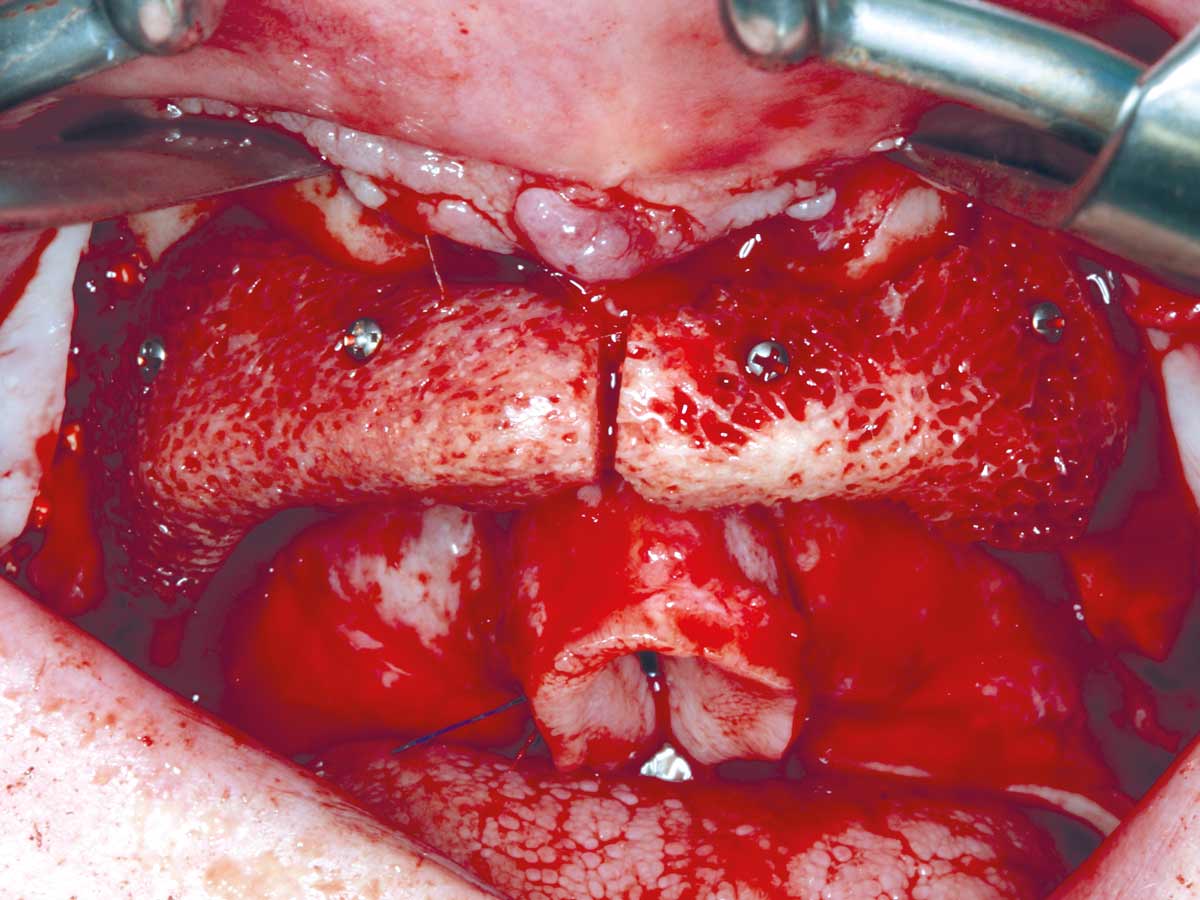

8/23 - Fixation of the first maxgraft® bonebuilder with osteosynthesis screws

Full arch reconstruction of the maxilla with maxgraft® bonebuilder - Dr. M. Erbshäuser

9/23 - Fixation of the second maxgraft® bonebuilder